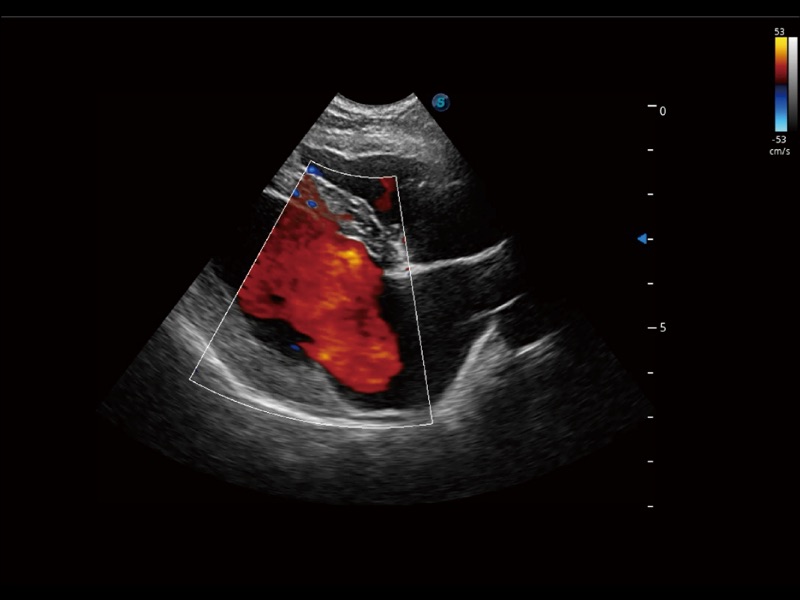

通過創(chuàng)新的 Matrix E自適應(yīng)濾波器和超長時(shí)間域算法,極大提升超低速微細(xì)血流的檢出能力,同時(shí)更精準(zhǔn)地濾除軟組織和噪聲信號,為獸用醫(yī)生提供以往無法通過常規(guī)血流獲得的疾病診斷信息。

通過色彩血流和實(shí)時(shí)寬景相結(jié)合,可觀察到完整的靜脈或動脈的血流,方便醫(yī)生檢查。實(shí)時(shí)掃查過程中,如有任何操作失誤也可以很容易地進(jìn)行回掃擦除,而不會中斷掃查。